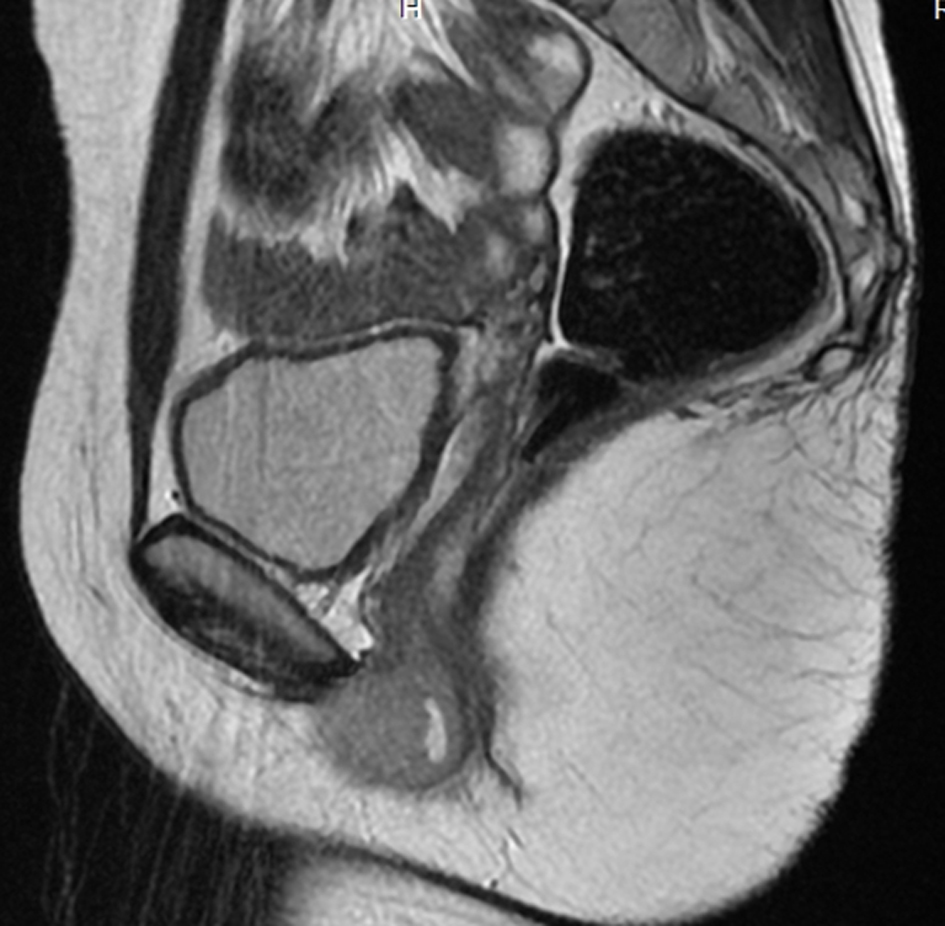

A 17-year-old girl presented with swelling at the clitorial region of few weeks duration. On examination, there was a swelling 3 × 2 × 2 cm at the clitorius. Computerized tomography (CT) scan of the abdomen and pelvis showed a right ovarian cyst of 3.5 × 2.5 cm in addition to the clitorial mass. She underwent diagnostic laparoscopy and left ovariectomy for the ovarian lesion and excision of the clitorial mass at the local hospital and was subsequently referred to us. Her performance status was 0, blood and serum chemistries were normal and lactate dehydrogenase was 405 U/L. The histopathological examination of the specimen from clitoris showed a neoplasm composed of round cells in large lobules separated by fibrocollagenous stroma, cells with scanty to moderate cytoplasm and vesicular nuclei, and many thin walled blood vessels were seen (Fig. 1). The tumor cells were strongly positive for MIC2, positive for neuron-specific enolase and negative for desmin, cytokeratin, myogenin and synaptophysin (Fig. 2). This was diagnostic of PNET/ES. The ovarian lesion was non-malignant. She was started on chemotherapy with vincristine, adriamycin, cyclophosphamide alternating with ifosphamide and etoposide and received local radiation 45 Gy/20# at ninth to 12th weeks. She achieved complete remission and chemotherapy was continued for 1 year. However, 4 months after treatment completion, she developed local recurrence in the form of well-defined mass 2 × 2 cm at the mons pubis. MRI showed multiple vulval deposits, deposits in the lower anterior pelvic wall, bilateral iliac bone, sacrum and femur (Fig. 3, 4). Bone scan showed multiple bone deposits and CT scan of chest showed multiple lung metastasis. She was given only supportive care and she died 6 months later.

![]() Click for large image | Figure 3. MRI T2WI SAG-lesion appears hyperintense. |